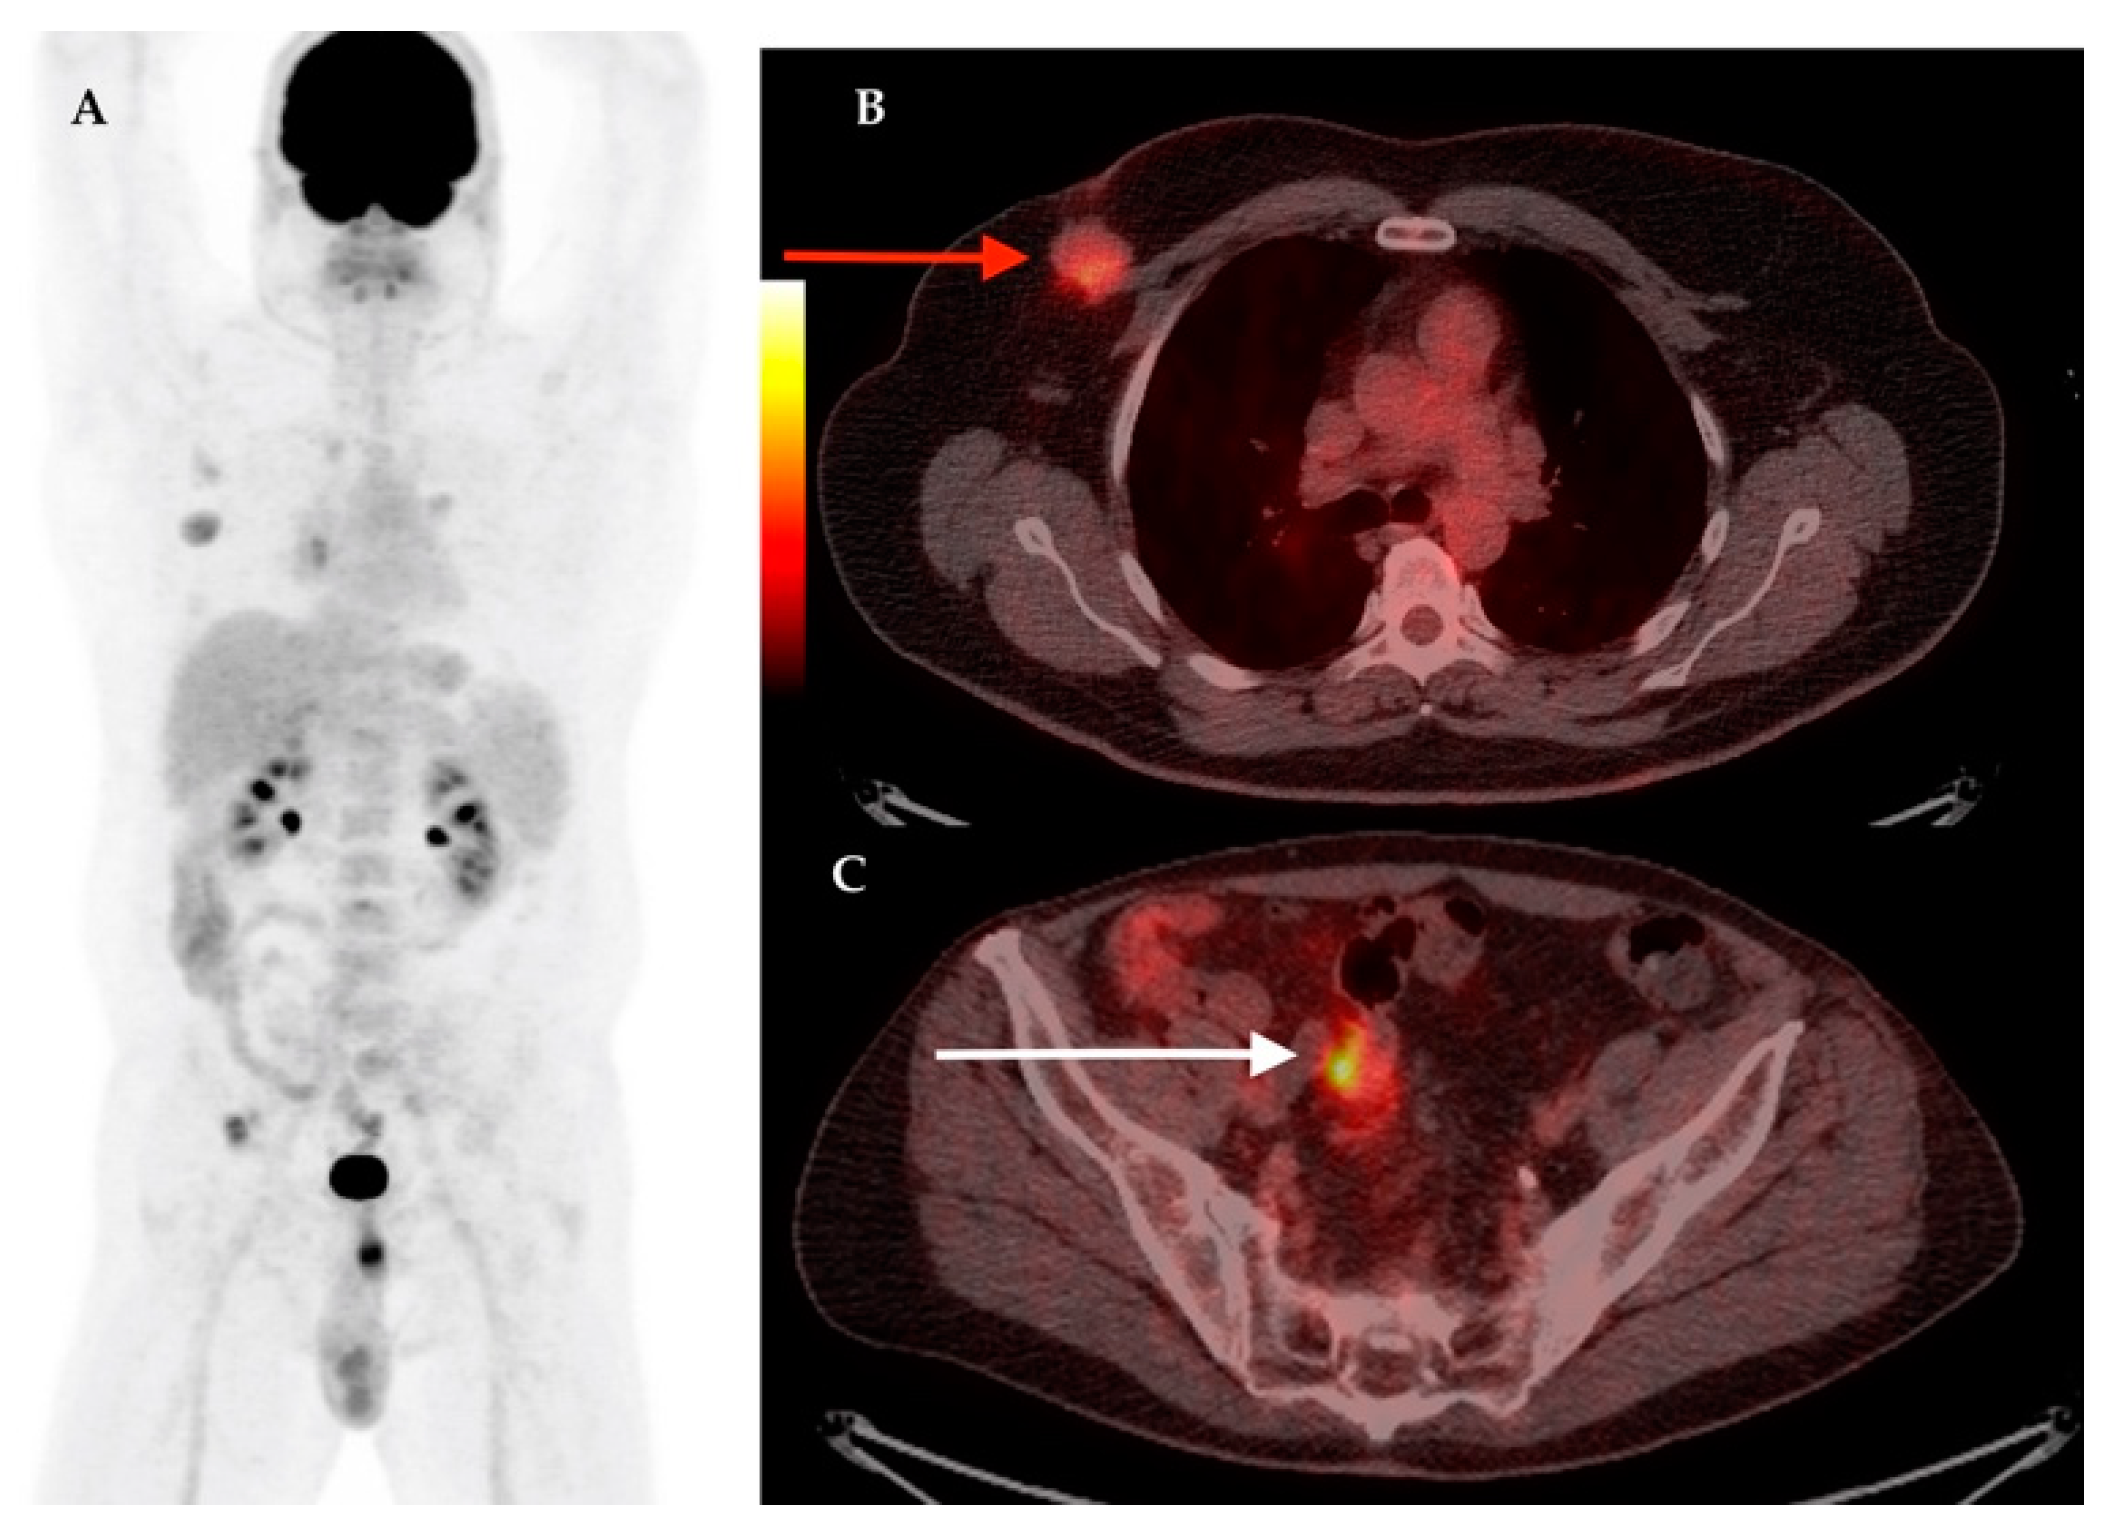

| 17 | 61 | IDC | RM + ALND | Yes | Yes | IIIB | LN | LN, Lu, M, Bn | 3.1 | Hodgkin Lymphoma | 11.6 |

| 21 | 61 | IDC | RM + ALND | Yes | Yes | IIC | LN | – | 2.38 | Thyroid cancer | 23.1 |